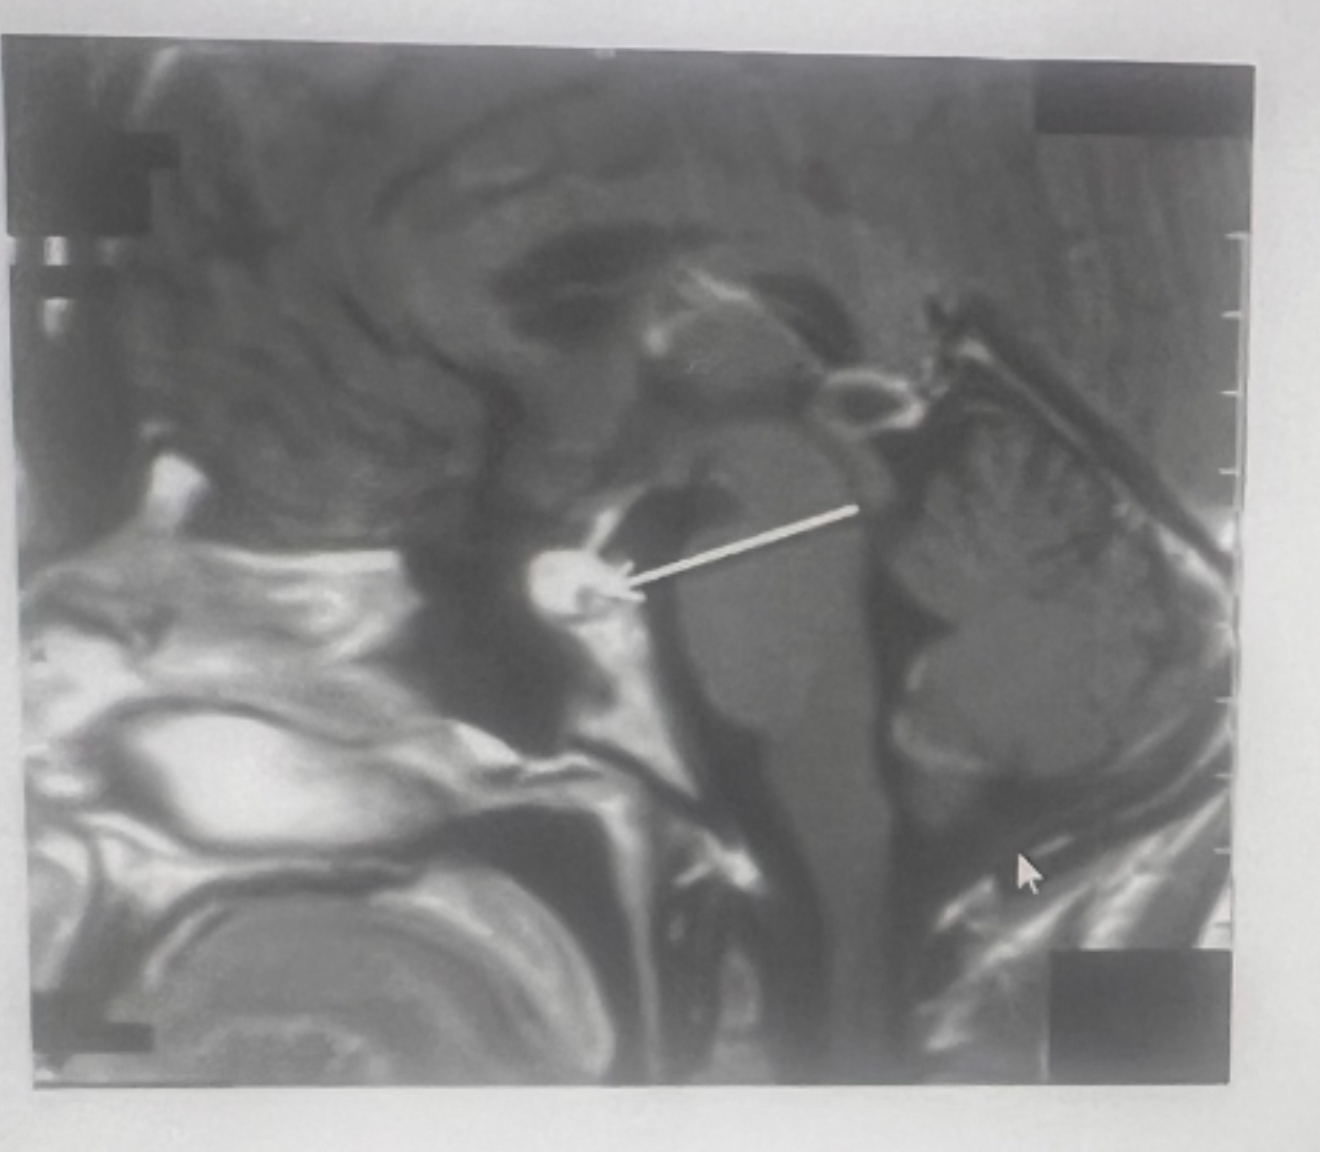

What does arrow indicate?

A

left parotid mass